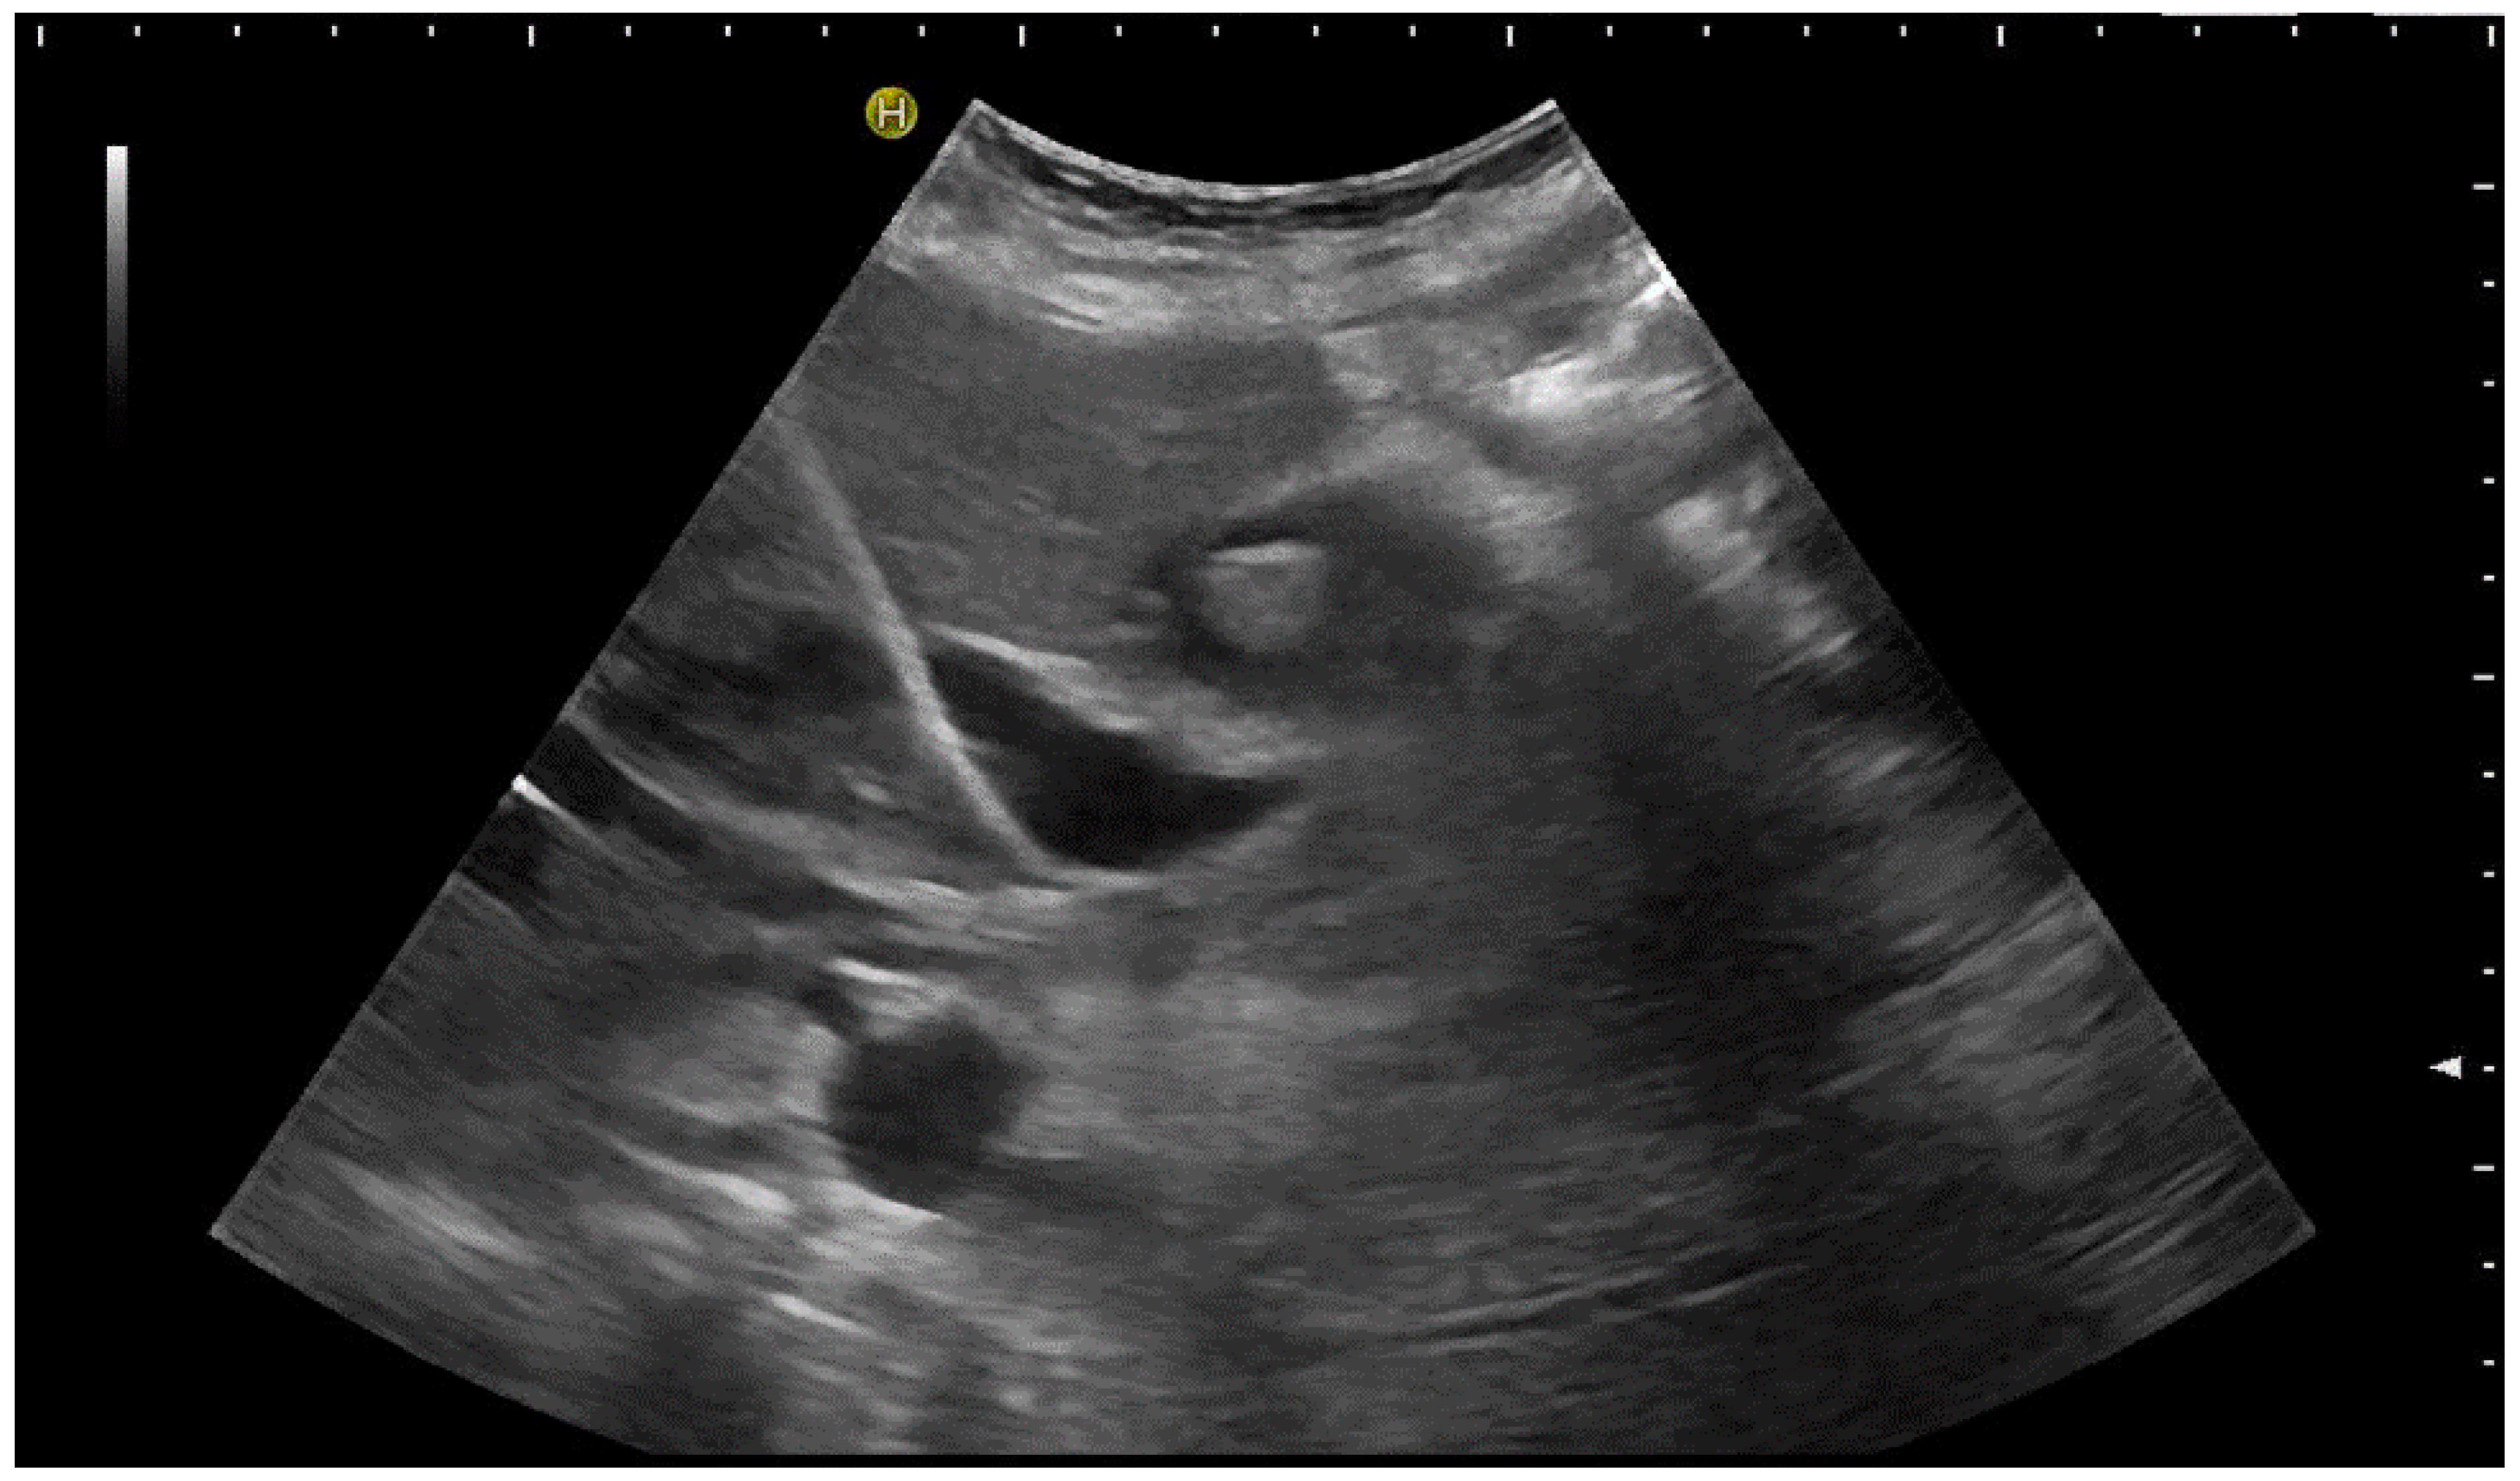

Usually, a Chiba needle of 21 G is used for the primary puncture. These needles can be depicted quite well in US given that the angle is pointed. Once the targeted bile duct has been accessed, the procedure is continued under fluoroscopic guidance by injecting a small amount of contrast agent to confirm correct needle placement and to visualise the biliary system fluoroscopically (Figure 6).

Figure 6.

Fluoroscopic confirmation of correct US-guided placement of the 24G needle.